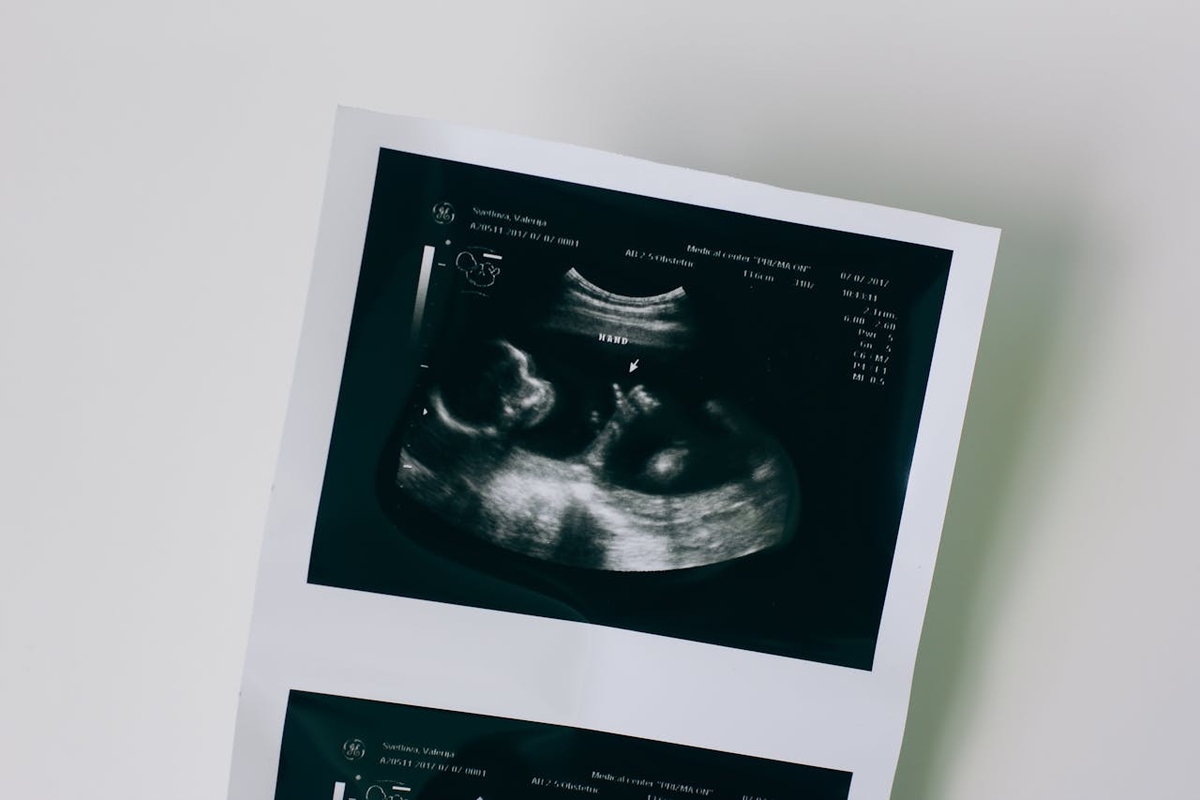

Uma técnica cirúrgica realizada ainda durante a gestação pode mudar o manejo de casos de vasa prévia, condição rara e potencialmente fatal para o bebê. A pesquisa, publicada na revista científica Prenatal Diagnosis, é liderada pelo pesquisador e cirurgião materno-fetal brasileiro Rodrigo Ruano (CRM 90870 SP), da University of Miami, e reúne um caso clínico recente, além de uma revisão sistemática de 54 procedimentos realizados internacionalmente. Os resultados apontam 100% de sobrevivência neonatal, alta taxa de sucesso técnico e ausência de complicações maternas relevantes.

A vasa prévia ocorre quando vasos sanguíneos do bebê passam pelo colo do útero sem proteção, o que os torna vulneráveis à ruptura. “Se houver rompimento das membranas, esses vasos podem se romper rapidamente, resultando em hemorragia fetal grave. Sem diagnóstico prévio, o risco de morte é elevado. Hoje, a conduta padrão é realizar cesariana programada entre 34 e 37 semanas para evitar esse risco — o que pode levar à prematuridade e à necessidade de internação neonatal”, explica Ruano.

A inovação está no uso da ablação a laser por fetoscopia, procedimento minimamente invasivo que coagula os vasos expostos ainda durante a gestação. “Isso reduz o risco de ruptura e pode permitir que a gravidez prossiga por mais semanas, aumentando a maturidade pulmonar e neurológica do bebê”, afirma o médico.

No caso apresentado no estudo, a gestante foi tratada na 31ª semana e conseguiu prolongar a gravidez até 36 semanas e 5 dias, quando entrou em trabalho de parto. O bebê nasceu saudável, por cesariana, a pedido da paciente.